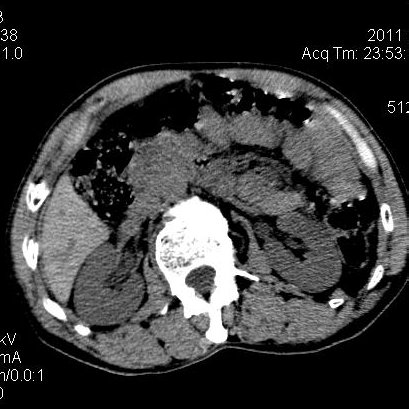

肝左叶发育异常

男性,55岁,骑摩托车摔倒后入院,自述右上腹疼痛

[backcolor=#FF0000]第一次诊断的时候也是这么肯定,可是床旁超声检查并没有发现明显异常,而且患者的一般症状都良好。还好临床只是保守治疗,没有立即手术,第二次复查的时候没有一点变化,又做了MRI检查,没有血肿,

这是一例肝左叶发育异常的,很个性吧~[/backcolor]